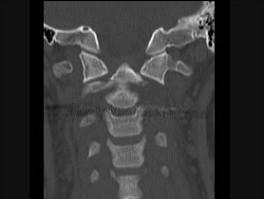

问题 本病例有颈部外伤,主诉颈部疼痛,活动受限,请结合所提供CT图像,选出最佳选项 ( )

选项 A、寰枢关节脱位 B、未见异常 C、C前弓骨折 D、C后弓骨折 E、C齿状突骨折

答案 E